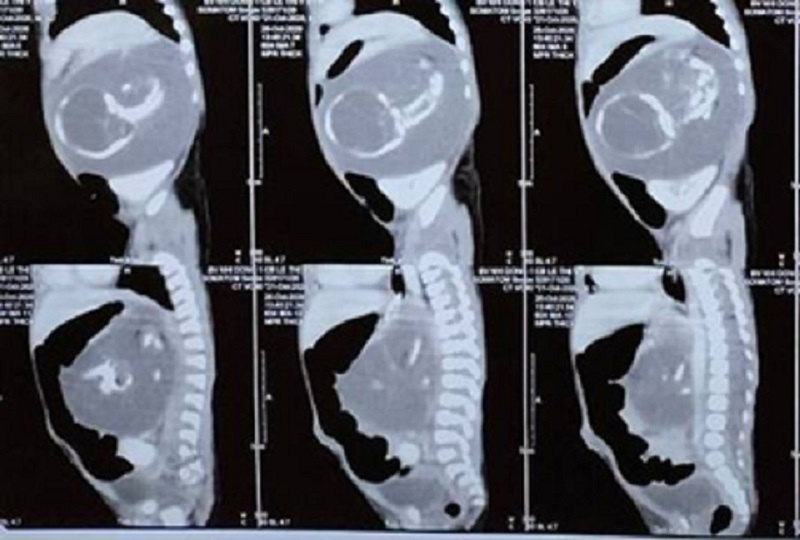

Khối thai được phát hiện trong bụng bệnh nhi trên ảnh chụp CT-Scan. (Ảnh:BVCC)

Qua siêu âm và CT-Scan ghi nhận một khối hỗn hợp trong bụng, nằm sau phúc mạc trái, kích thước 5,3cm x 8,1cm. Khối u to có mô mỡ, cột sống, hộp sọ, xương dài đẩy thận xuống vùng hố chậu, đẩy tụy ra trước. Bác sĩ chẩn đoán dây là trường hợp “thai trong thai” và chỉ định phẫu thuật.